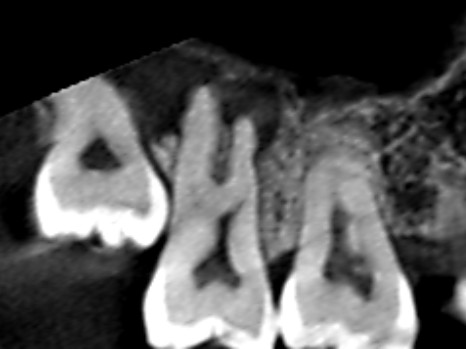

初診時の冠状断のCT画像です。

赤い矢印の先に膿の黒い影がみられます。膿は大きく、第二大臼歯にある3本の根の全てを覆っていました。